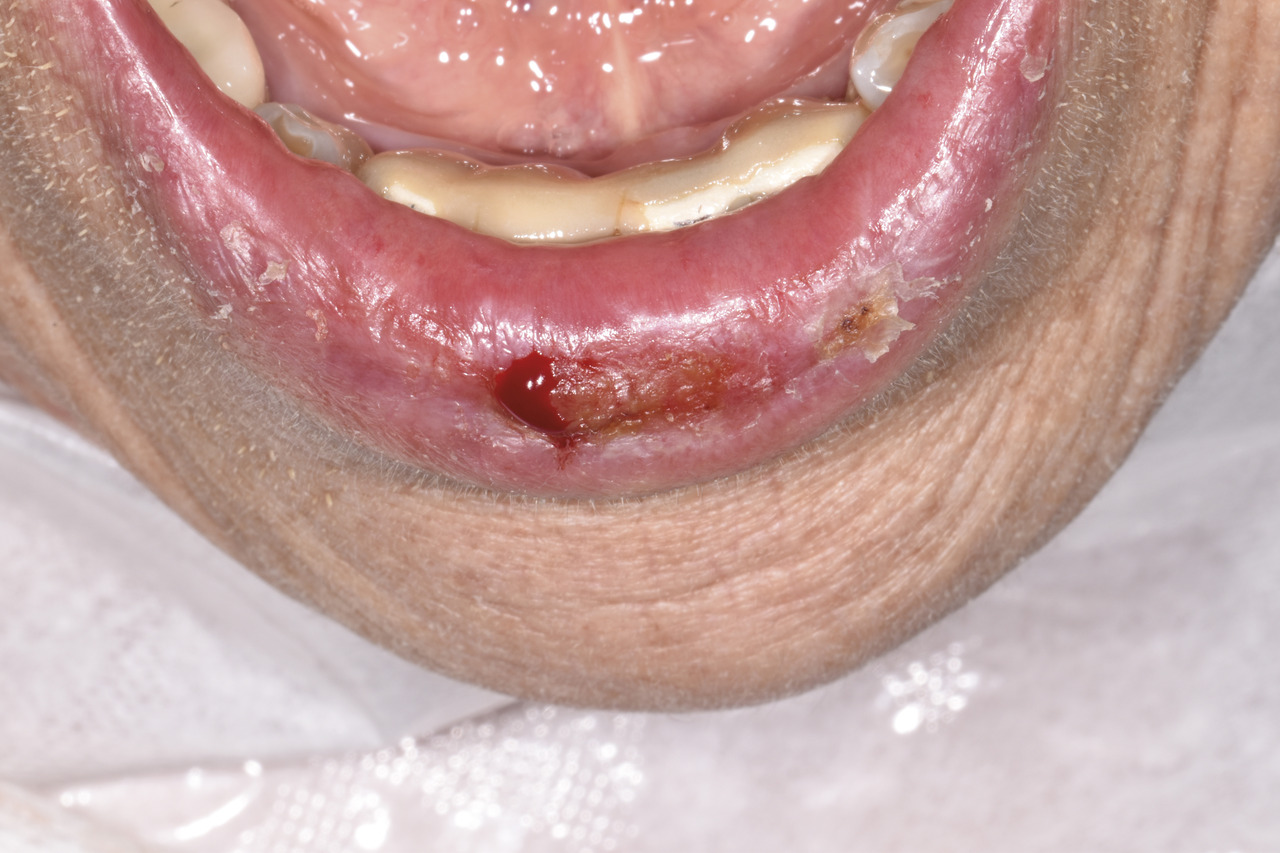

Une patiente de 86 ans consulte pour une lésion érosive douloureuse de la lèvre inférieure saignant au contact et présente depuis plusieurs mois (figure ). Dans ses antécédents, on note un asthme et une allergie au pollen pour laquelle elle est traitée quotidiennement par antihistaminiques. Elle ne fume pas.

Cliniquement, les lésions peuvent se manifester sous forme réticulée : asymptomatiques, bilatérales et symétriques. Mais la forme érosive est la plus fréquente : association de zones érosives douloureuses nettement limitées à un fond érythémateux. La localisation gingivale est la plus décrite dans la littérature scientifique.1 Pour cette patiente, la lésion était labiale inférieure, avec une zone érosive, une desquamation et une ébauche de réticulations à la périphérie de la lésion.